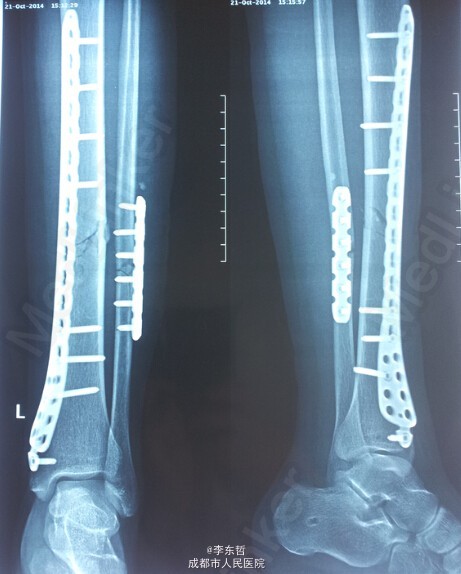

左下肢胫腓骨骨折伴右下肢内外踝骨折一例

患者,女,26岁,外伤致左下肢胫腓骨骨折、右下肢内外踝骨折,入院后右侧临时石膏固定、左侧骨骨牵引10天后,双侧同时手术,左侧胫骨采用MIPPO技术内侧钢板固定。